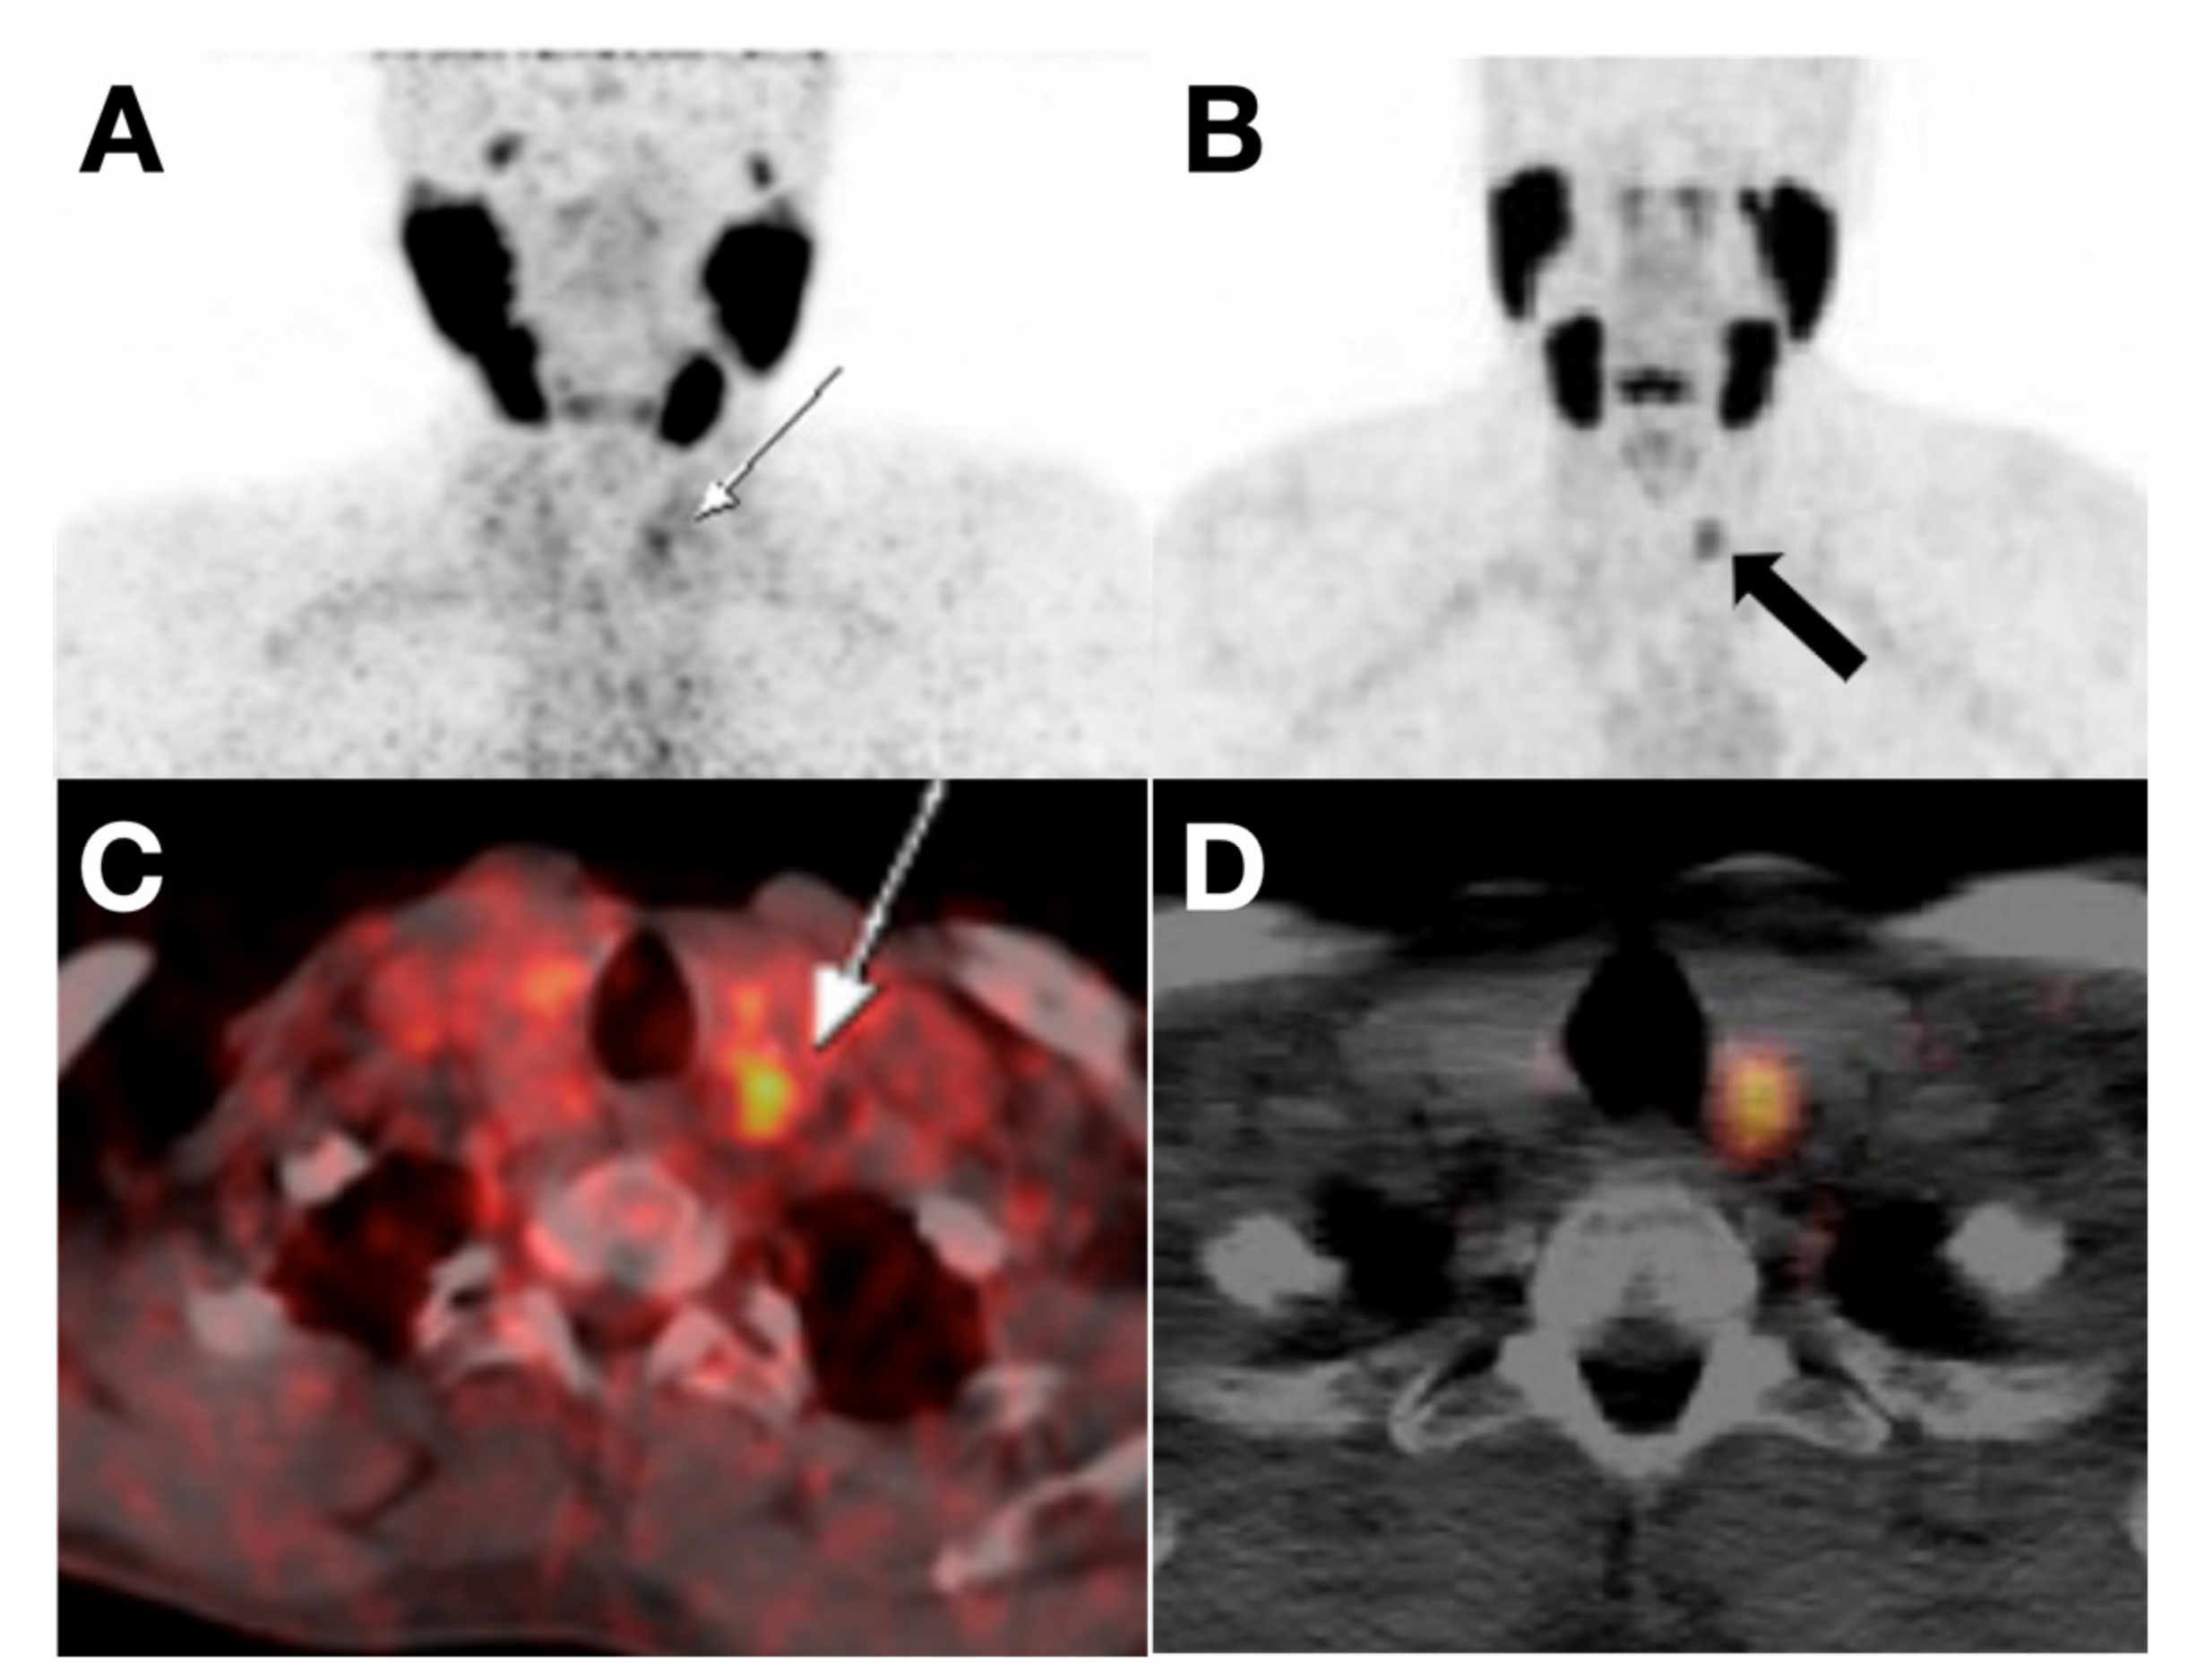

- Uprimny, C.; von Guggenberg, E.; Svirydenka, A.; Mikołajczak, R.; Hubalewska-Dydejczyk, A.; Virgolini, I.J. Comparison of PET/CT Imaging with [18F]FDOPA and Cholecystokinin-2 Receptor Targeting [68Ga]Ga-DOTA-MGS5 in a Patient with Advanced Medullary Thyroid Carcinoma. Eur. J. Nucl. Med. Mol. Imaging 2020, 1–2. [Google Scholar] [CrossRef]